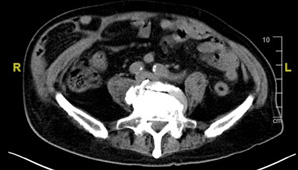

斷層掃描顯示右下腹巨大腹壁疝氣併腸外露。